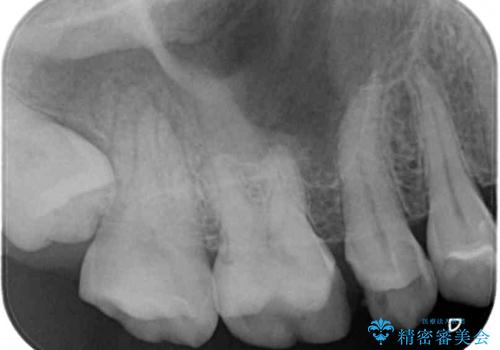

- 他院で治療を開始したものの抜歯が必要と言われ、何とか残せないものかとのことで来院された患者様です。

下顎大臼歯は歯冠部分が残っておらず、保存が難しいように思えましたが、まずは根管治療を行った上で補綴治療を行うこととしました。

上顎臼歯は、おそらく銀歯を外して仮詰めされていたため、再度形を整え、セラミックインレーにて修復治療を行うこととしました。